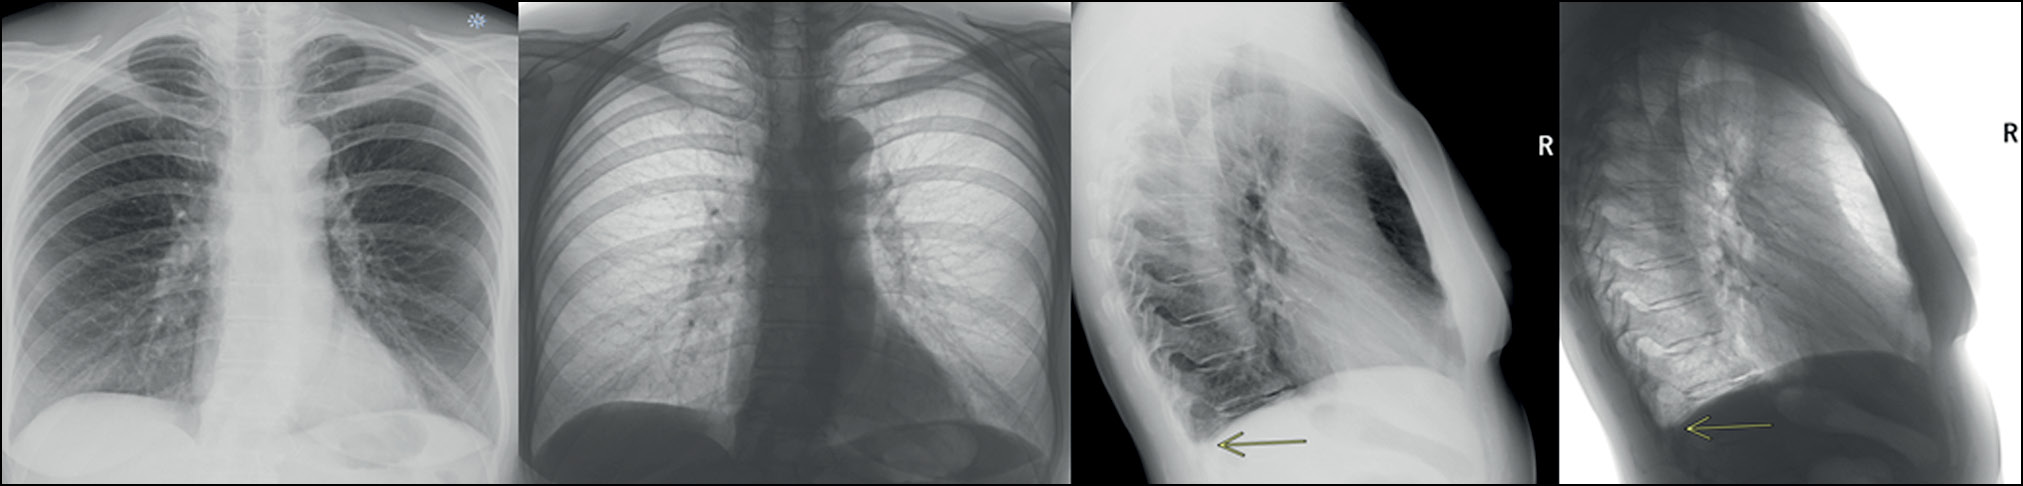

Выявлен также случай необнаружения очаговой тени, которая в прямой проекции проецируется на тень средостения и может быть выявлена только на снимке в боковой проекции (рис. 8).

Рис. 8. На боковой проекции визуально определяется очаг в проекции верхней доли (все программные обеспечения на основе технологий искусственного интеллекта закономерно его не определили ввиду обработки только прямой проекции).

В другом случае ИИ-сервис, опять же по причине невозможности обработки боковой проекции, не определил фиброзные изменения (рис. 9).

Рис. 9. На боковой проекции определяются фиброзные изменения в заднем косто-диафрагмальном синусе справа, которые не видны на прямой проекции (сервис искусственного интеллекта их не определил ввиду обработки только прямой проекции). Аналогично данным изменениям сервис может «пропустить» минимальный плевральный выпот.